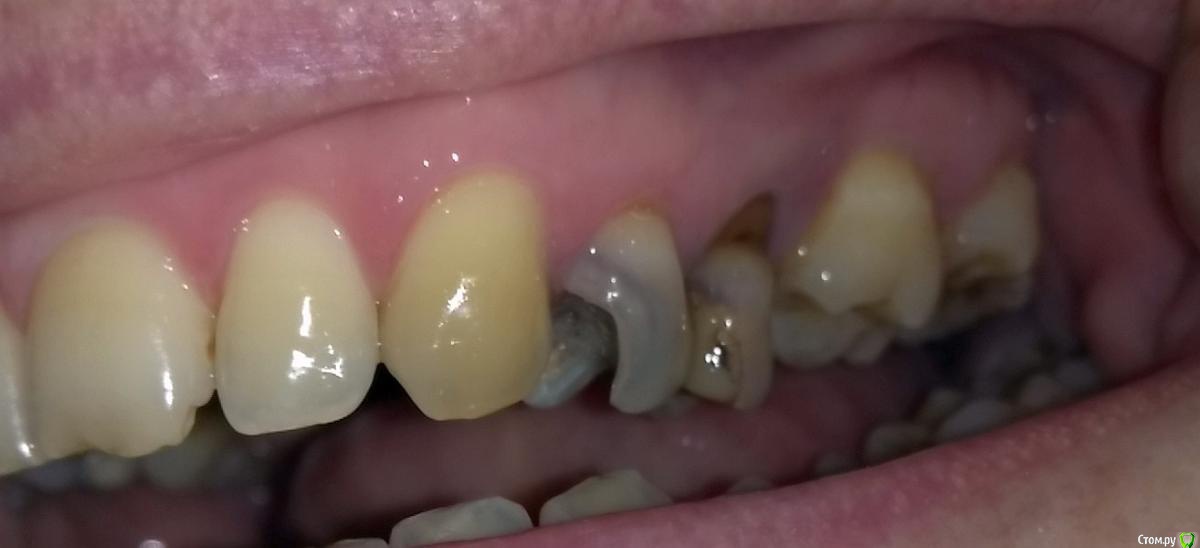

Александр9 Опубликовано 16 ноября, 2015 Поделиться Опубликовано 16 ноября, 2015 я много лет не был в стоматологии и пока плохо представляю с чего начать. Из основных проблем - отсутствуют по зубу с каждой стороны на верхней челюсти, один зуб наполовину разрушился (что и стало "последней каплей"), ну и наверное надо будет несколько зубов подлечить. Собираюсь пойти для начала на предварительную консультацию. Видимо имеет смысл обратиться в 2-3 места. Чтобы эти предварительные консультации были максимально эффективными, посоветуйте пожалуйста:1) к какому специалисту мне надо обращаться (ортодонту, хирургу, терпавту)?2) какие снимки мне пригодятся: рентген всей челюсти, рентген отдельных зубов, томография челюсти (в т.ч. числе чтобы в дальнейшем можно было бы посоветоваться здесь на форуме)? Ссылка на комментарий

Александр9 Опубликовано 20 ноября, 2015 Автор Поделиться Опубликовано 20 ноября, 2015 (изменено) У меня разрушен 24 зуб и очень плох 25. На другой стороне 14,15 также не совсем хороши (16 отсутствует как и 26).Мне предлагается поставить коронки на эти четыре зуба. Но перед этим по-видимому надо подлечить остальные зубы: обновить несколько пломб и почистить каналы.Хотелось бы растянуть (из финансовых соображений) сроки лечения. Т.к. хочется поскорее сделать "красивым" 24 зуб (виден если широко улыбаться), то посоветуйте пожалуйста что целесообразно сделать в первую очередь? Изменено 20 ноября, 2015 пользователем Александр9 Ссылка на комментарий

DmitrySH Опубликовано 20 ноября, 2015 Поделиться Опубликовано 20 ноября, 2015 Начните с лечения каналов 24, 25, 14, 15.Впринципе 25 нормально запломбирован по снимку, но надо оценить геметичность пломбы и понять чем запломбировано.Кариес на 27, 46. Остальные пломбы визуально смотреть. Далее, у Вас из-за длительного отсутвия 16, 26 - произошло смещение зубов. Соответвенно нужна консультация ортодонта.Если заниматься ортодонтическим лечением, то верхние 15,14,24,25 на время ортодонтии восстановить пломбами или временными коронками ( по ситуации) после ортодонтии изготовление постоянных коронок Ссылка на комментарий